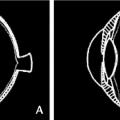

Décollement de rétine rhegmatogène

decollement de la retine